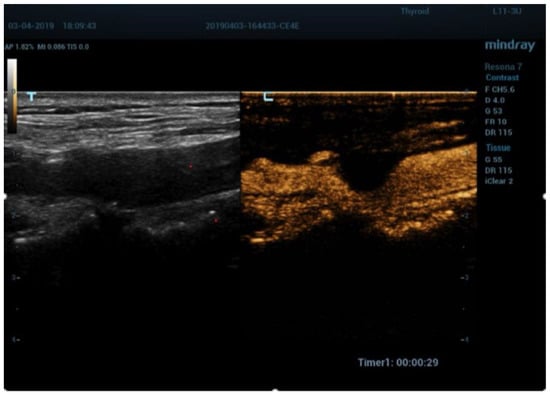

- Cantisani, V.; Di Leo, N.; David, E.; Clevert, D.A. Role of CEUS in Vascular Pathology. Ultraschall Med. 2021, 42, 348–366. [Google Scholar] [CrossRef] [PubMed]

- Fresilli, D.; Di Leo, N.; Martinelli, O.; Di Marzo, L.; Pacini, P.; Dolcetti, V.; Del Gaudio, G.; Canni, F.; Ricci, L.I.; De Vito, C.; et al. 3D-Arterial analysis software and CEUS in the assessment of severity and vulnerability of carotid atherosclerotic plaque: A comparison with CTA and histopathology. Radiol. Med. 2022, 127, 1254–1269. [Google Scholar] [CrossRef] [PubMed]

- Clevert, D.A.; Sommer, W.H.; Helck, A.; Saam, T.; Reiser, M. Improved carotid atherosclerotic plaques imaging with contrast-enhanced ultrasound (CEUS). Clin. Hemorheol. Microcirc. 2011, 48, 141–148. [Google Scholar] [CrossRef] [PubMed]